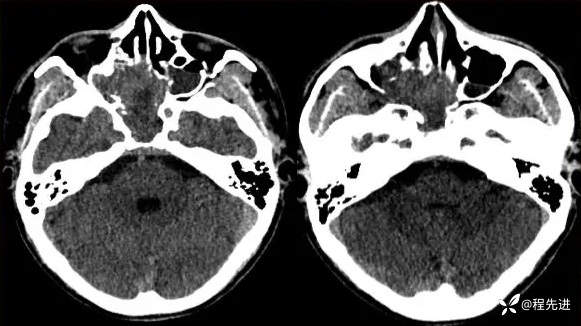

【患者信息】:男,24岁

【现病史及既往史】:患者1月前无明显诱因出现右脸麻木,之后出现复视,20天前发出现右眼失明伴头痛

CT: